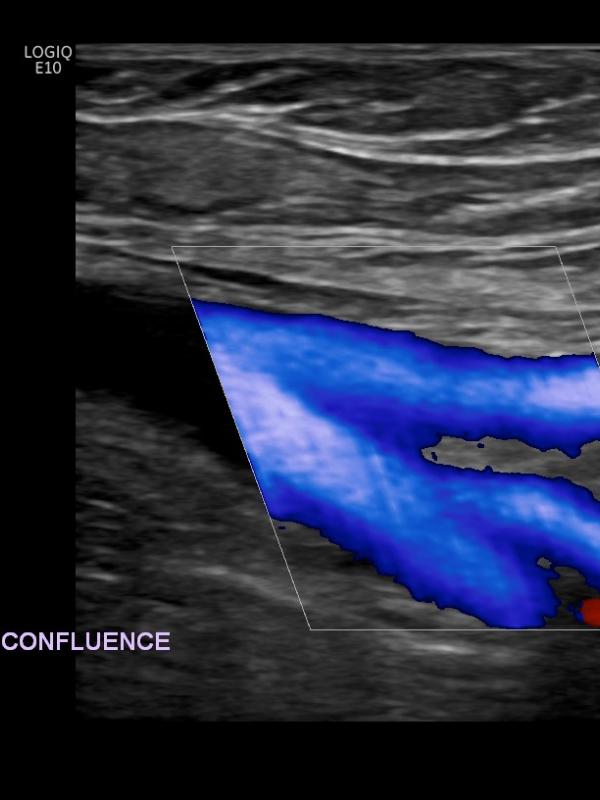

Venous ultrasound

Ultrasound imaging of the venous system is used to evaluate the vessel and returning blood flow from upper or lower extremities. Referring providers order venous ultrasounds for a number of reasons. The most common reasons are: leg pain or swelling, varicose veins, or evaluation for a suspected blood clot.

Venous ultrasound FAQ

- What is the preparation for a venous ultrasound examination? There is no required preparation for a venous ultrasound.

- What is a vein mapping ultrasound? A detailed evaluation of the entire venous system in your lower extremities. The sonographer will first evaluate for a blood clot, then will map out the superficial venous system and evaluate for valve incompetency